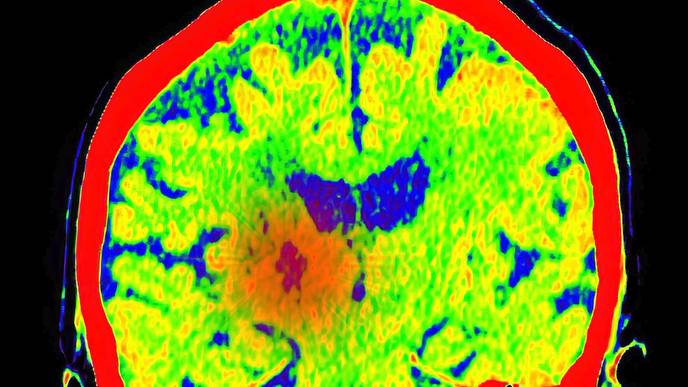

Led by Ludwig Lausanne’s Johanna Joyce, Spencer Watson and alumnus Anoek Zomer and published in the current issue of Cancer Cell—where it is featured on the cover—the study describes how these scars enable the regrowth of tumors and identifies drug targets to sabotage their malignant support. It also demonstrates the efficacy of such combination therapies in preclinical trials using mouse models of GBM.

These technologies include the analysis of global gene expression in individual cells, the comprehensive analysis of proteins in the tissues as well a workflow and AI-powered suite of analytical methods for the spatial analysis of tissues named hyperplexed immunofluorescence imaging (HIFI). Recently developed by Watson and colleagues in the Joyce lab, HIFI permits the simultaneous visualization of multiple molecular markers in and around cells across broad cross-sections of tissues, enabling the generation of granular maps of the tumor microenvironment.